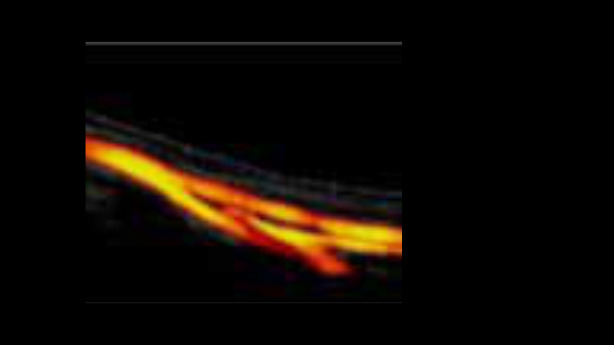

EcĂłgrafo Zeus presenta una interfaz fĂĄcil de usar y funciones sencillas para realizar exploraciones eficientes. Sus versĂĄtiles capacidades abarcan la ecografĂa abdominal, vascular, de partes peque?as y musculoesquelĂ©tica, lo que aumenta la confianza en el diagnĂłstico.